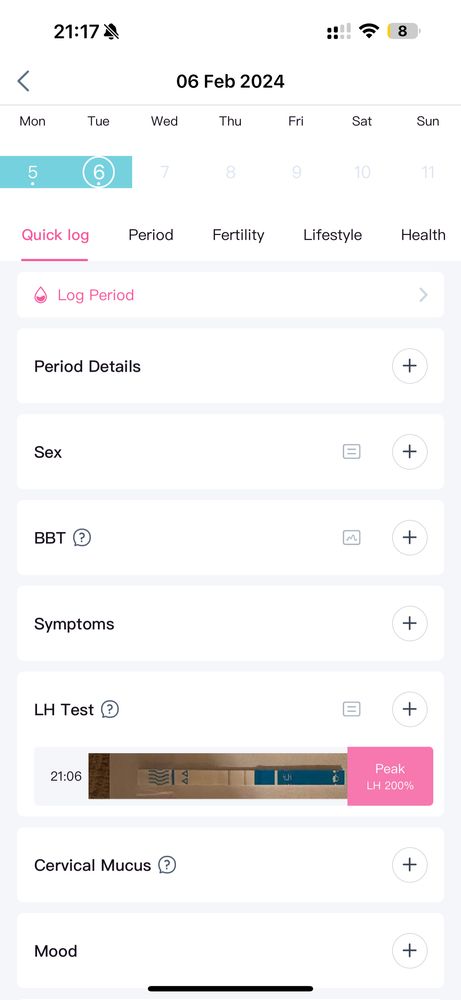

Наталья, а почему тогда не снижается ЛГ, не знаете? На сколько я знаю, то должно снижаться.. вот Фемометр мне показывает сегодня пик🫠

Наталья, от первого тоже говорил пик, и тоже 200%🤔